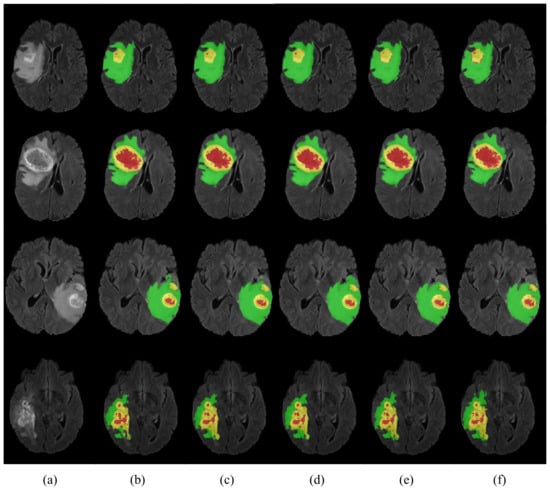

The results in Table 4 show that the proposed HMNet has the advantage of low model complexity compared to the non-lightweight network. Compared with the traditional 3D U-net, the number of parameters of our network was reduced to a fifth, and the amount of computation was reduced by 1540.1 G. The Dice of HMNet were 7.5%, 3.9%, and 8.6% higher than 3D U-net in ET, WT, and CT, respectively, which means that our network is more accurate than 3D U-net for brain tumor segmentation. Figure 6 shows more obviously that our network greatly improved segmentation accuracy compared to 3D U-net. It can be observed in Figure 7 that our network can extract more detailed information than 3D U-net. Table 4 shows that our network can achieve excellent segmentation results in WT and TC compared with the other non-lightweight network. Therefore, the HMNet is competitive in non-lightweight networks.

To verify the efficiency of our proposed network, we compared the performance of HMNet and other high-performing lightweight networks. Table 5 and Figure 7 display the experimental results. We retrained the network in Table 5 on the BraTS 2020 dataset.

Table 5 shows that the HMNet uses only about a quarter of the parameters of 3D ESP-Net, while the Dice of ET, WT, and TC are improved greatly, increasing by 9.1%, 3.0%, and 3.7%, respectively. Compared with DMF-Net, HMNet has 79.4% fewer parameters, while the Dice coefficients of WT and TC have improved by 0.2% and 0.6%, respectively. HDC-Net is currently the lightest brain tumor segmentation network, but the network is so light that it leads to poor segmentation metrics. Compared with HDC-Net, the Dice coefficients of ET, WT, and TC of the segmentation results of HMNet improved by 1.4%, 0.50%, and 2.60%, respectively, and the Hausdorff distances of ET and TC were shortened by 11.1 mm and 7.1 mm, respectively. As we can see in Figure 7, our network is more accurate than other networks in segmenting brain tumor boundaries. The above analysis shows that the proposed network is competitive in lightweight networks, and the proposed improvement direction is feasible.

Figure 7. Visualization of segmentation results. Each row represents a different sample. (a) is the modality of Flair. (bf) are the segmentation results of 3D Unet, DMF-Net, HDC-Net, HMNet, and ground truth. The red area is necrosis and non-enhancing, the yellow area is enhancing tumor, and the green area is edema.